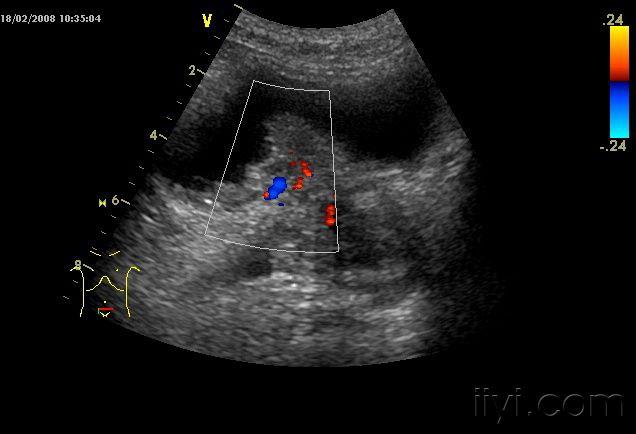

早期膀胱癌的彩超图

典型膀胱占位两例!(膀胱癌)

超声入门贴41-----膀胱癌

超声入门贴41膀胱癌

典型的膀胱癌一例

一例膀胱癌的声像图

膀胱内实性占位考虑为膀胱癌

膀胱占位考虑膀胱癌

典型膀胱癌声像图一例

彩超提示膀胱内实质性占位病变,考虑膀胱肿瘤膀胱镜检示右侧壁菜花状

【请教】膀胱癌?

膀胱占位

【原创】膀胱癌